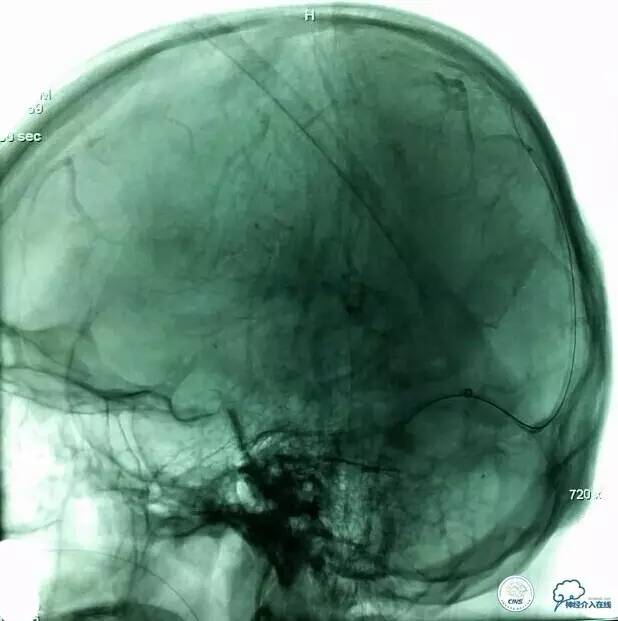

▼导丝,支架位置:

▼支架释放:

▼确定微管位置: